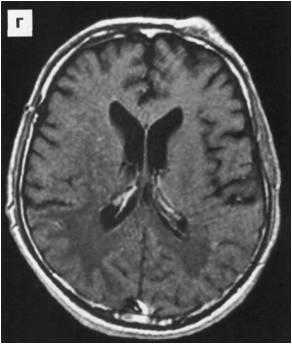

МРТ головного мозга. Аксиальная Т2-взвешенная МРТ. Расширение борозд и диффузные очаги.

Прогрессирование атрофии при прослеживании МРТ головного мозга в динамике происходит очень быстро.